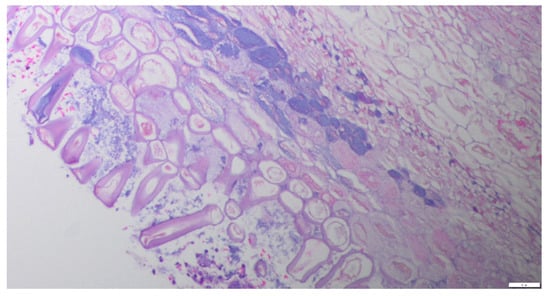

Immunohistochemical Expression of Integrin αvβ6 in Surgically Resected Pulmonary Inflammatory Lesions Mimicking Malignancy on 18F-FDG PET/CT: Implications for the Specificity of 68Ga-Trivehexin PET/CT

by Muin Tuffaha, Amro Tuffaha, Wael Hananeh, Mohammad Khalifeh, Jenny Sonke and Michael Starke

Biomolecules 2026, 16(4), 602; https://doi.org/10.3390/biom16040602 - 18 Apr 2026

18F-fluorodeoxyglucose (FDG) PET/CT is widely used for the evaluation of pulmonary lesions but lacks specificity, as increased FDG uptake is frequently observed in inflammatory and reparative processes. This limitation may lead to false-positive interpretations and unnecessary surgical resections. This study aimed to [...] Read more.

18F-fluorodeoxyglucose (FDG) PET/CT is widely used for the evaluation of pulmonary lesions but lacks specificity, as increased FDG uptake is frequently observed in inflammatory and reparative processes. This limitation may lead to false-positive interpretations and unnecessary surgical resections. This study aimed to evaluate the immunohistochemical expression of integrin αvβ6 in 18 surgically resected pulmonary lesions that were falsely classified as malignant on FDG PET/CT, in order to find out if 68Ga-Trivehexin PET/CT could have superior preoperative diagnostic specificity. Histopathological examination classified all lesions as non-neoplastic inflammatory processes of varying etiologies. Integrin αvβ6 expression was detected in all immunohistochemically examined tissue specimens (18/18 cases (100%)), with moderate membranous overexpression in 2/18 cases (11.11%) and strong membranous overexpression in 16/18 cases (88.89%) observed in the alveolar and bronchial epithelium of inflammatory lung lesions. Our findings indicate that integrin αvβ6 is upregulated not only in neoplastic lung tissue but also in inflammatory lesions, suggesting that integrin αvβ6 may have limited specificity for distinguishing primary neoplastic from inflammatory pulmonary lesions when used alone. Its interpretation requires integration with other clinical imaging modalities and histopathological data. Full article